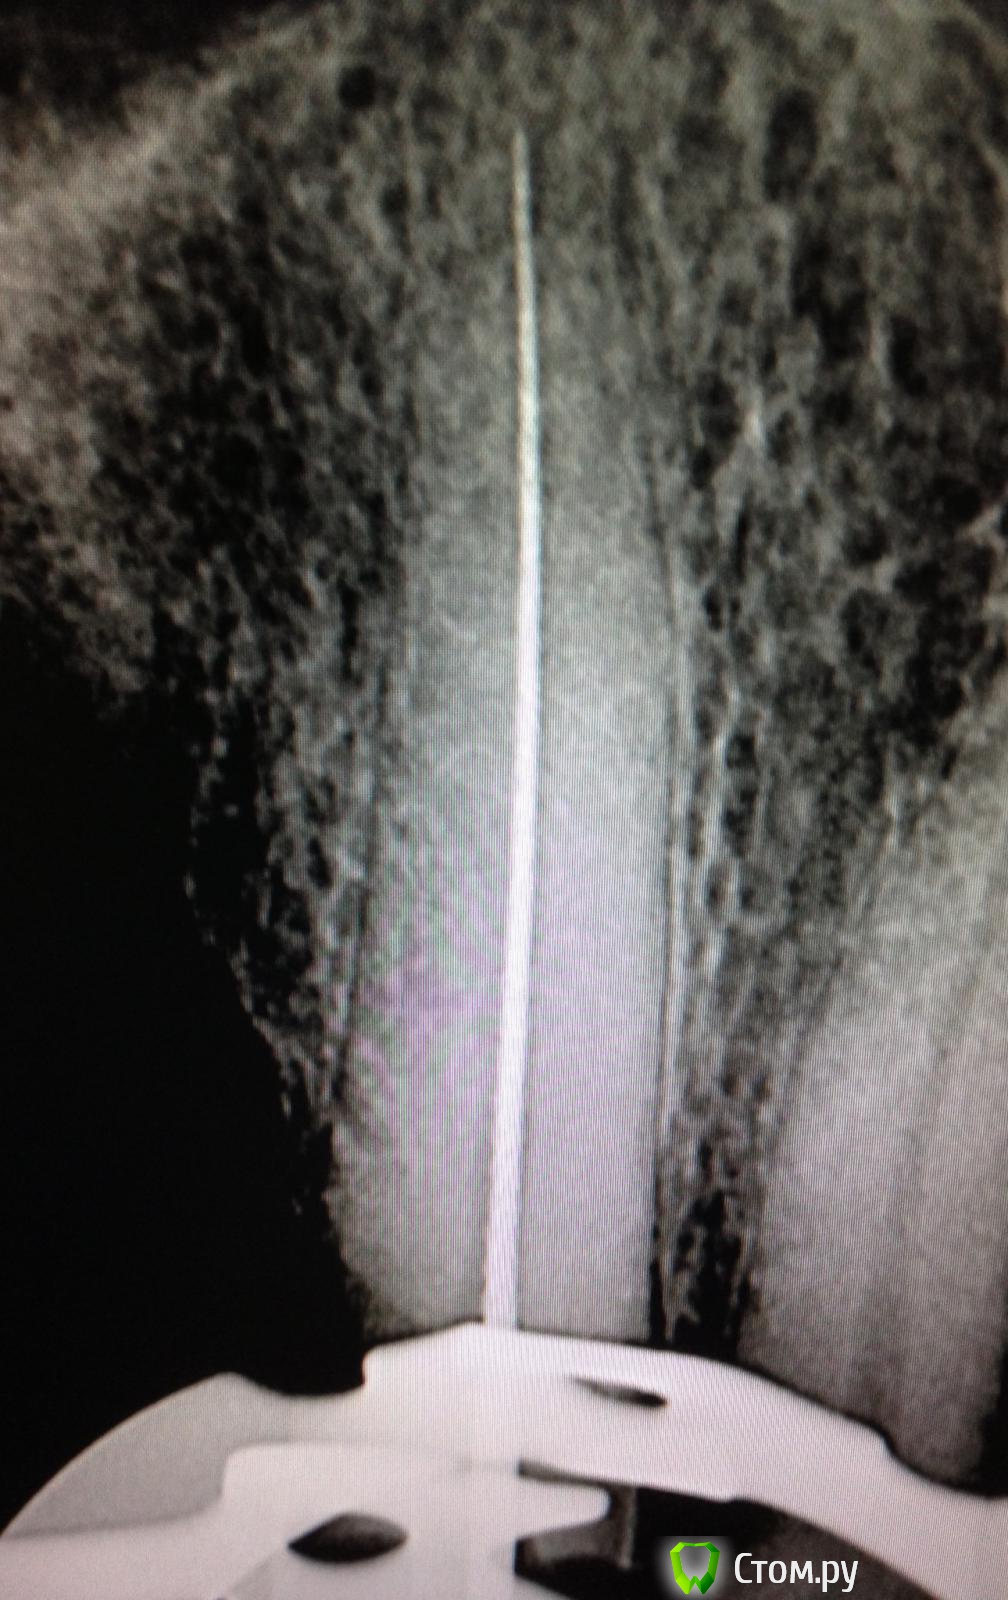

SSTi Опубликовано 19 сентября, 2014 Автор Поделиться Опубликовано 19 сентября, 2014 Новая кривулина. Начало. Попросил доктор знакомый полечить...)Неделю боли на накусывание. Иррадиируют в левый висок. Зуб 27. Внешне все ок. Маааленькая точечка в фиссуре. Шестерки нет. Делаю снимокТааааак. Позвонил доктору, сказал , как я счастлив, и приступил. Преп. Коффер. Дистально на уровне десны. Небный дистальный бугор ушел. В полости небольшой склероз. Мб сразу прошелся. Вообще без проблем. Только при хрусте файлов я чуть вспотел в области крестца))) расширились до 30.04 и дальше ручками 35.02. Мб 2 пока не нашел. Сулькус раскрыл - но там глухо. Поищем в следующий раз. Дистальный сначала только до уровня , как на снимке, потом прошел. Тоже 30.04 и 35.02. Небный- последние 3-4 мм дались с трудом. Но прошли. До 35.04 и 40.02. Мылись, сушились, кальцифицировались. Времянка. Продолжение следует 3 Ссылка на комментарий